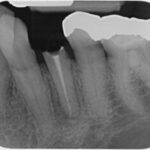

Zahn mit unvollständiger Wurzelfüllung und chronischer Entzündung an der Wurzelspitze

Nach medikamentösen Einlagen und vollständiger Wurzelfüllung – die Entzündung heilt ab